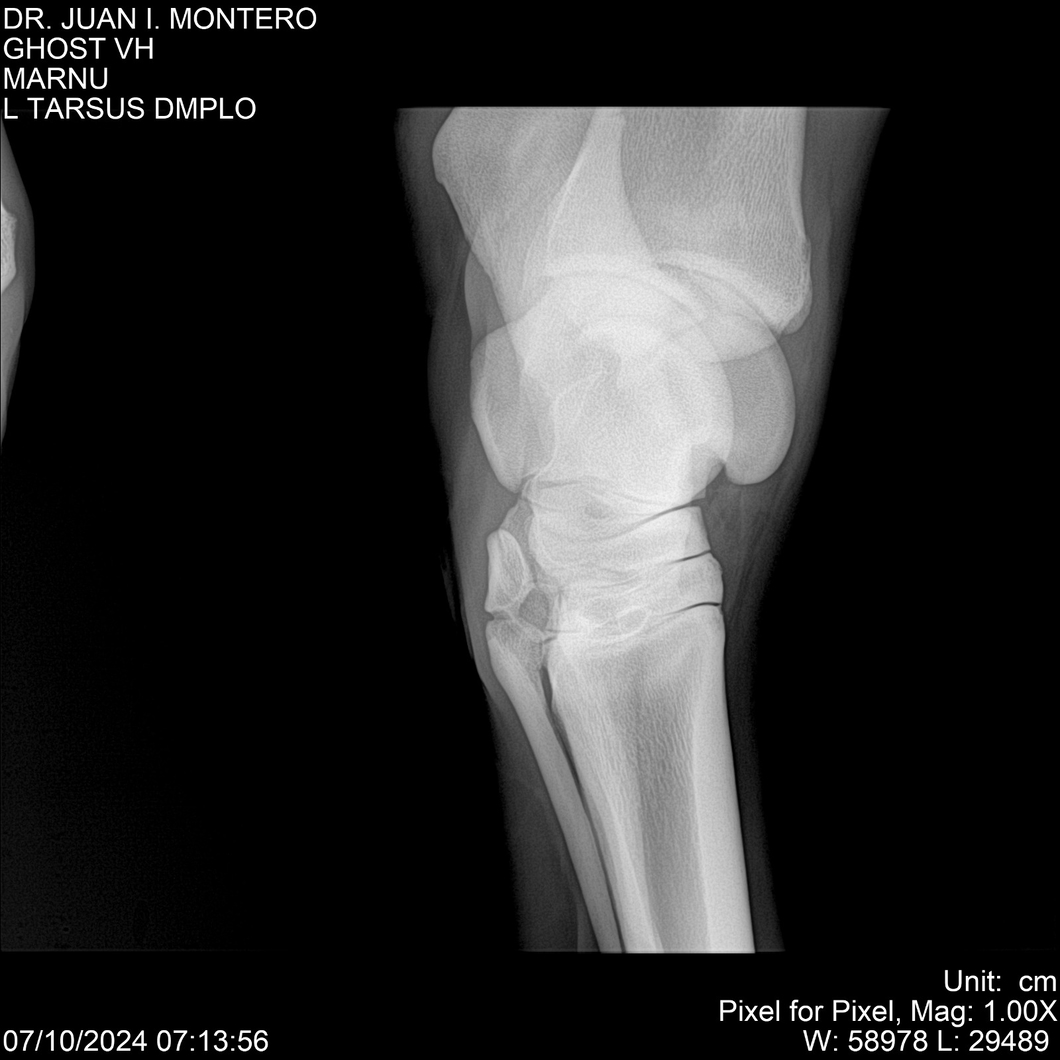

LOTE 15, GHOST VH 🔥 🔥 🔥 Lote Anterior Volver al remate Lote Siguiente Ficha Contacto Montevideo - Ficha del Lote Identificador: #282525 Categoría: Yeguarizos Montevideo - 69 Visualizaciones ClicData Contacto Empresa: Abelenda N. R., Walter Hugo Nombre*: Teléfono* : E-mail* : Mensaje Enviar Registrese gratis Este contenido Exclusivo está disponible sólo para usuarios registrados Ingresar